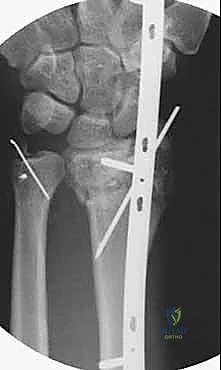

تعتمد هذه التقنية المتقدمة على مبدأ إبقاء المفصل مشدوداً ومثبتاً من الخارج. الصفيحة تعمل كـ "جسر" يعبر فوق منطقة الدمار الشامل في العظم، وترتكز على عظم سليم في الساعد وعظم سليم في اليد. هذا الجسر يمنع العظم المفتت من الانهيار ويسمح للشظايا الصغيرة بالالتئام في مكانها الصحيح بفضل الشد الطبيعي للأربطة المحيطة.

3. إدخال الصفيحة الجسرية (Plate Insertion)

بمهارة فائقة، يتم تمرير الصفيحة المعدنية المصنوعة من التيتانيوم تحت الجلد وفوق الأوتار عبر الشقين، بحيث تعبر مفصل الرسغ بالكامل متجاوزة منطقة الكسر المفتتة دون العبث بها.

5. وضع البراغي النهائية (Screw Insertion)

يتم تثبيت الصفيحة بقوة باستخدام براغي متطورة (Locking Screws) في عظم الساعد السليم وعظم المشط في اليد. هذه البراغي تلتحم بالصفيحة لتشكل هيكلاً صلباً للغاية لا يتأثر بالحركة.

6. التحقق الإشعاعي (Fluoroscopic Verification)

أثناء العملية، يستخدم الدكتور هطيف جهاز الأشعة المباشر للتأكد من المحاذاة المثالية للعظم واستعادة الطول والزوايا التشريحية الصحيحة للرسغ.